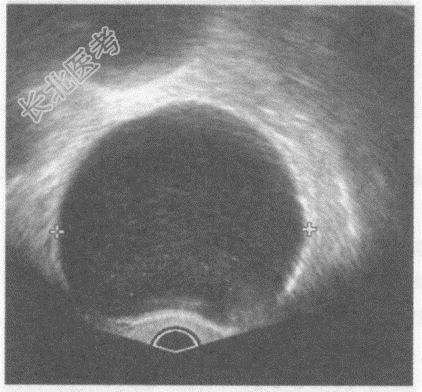

- 单项选择题临床资料:女性患者, 57岁,自述下腹部进行性增大不适半年余。妇科内诊: 左附件区触及拳头大肿物。

超声综合描述:经阴道扫查左附件区可见8.0cm×6.1cm无回声区, 边界清晰,形态规则, 内见少许分隔,CDFI: 无回声周边可见条样血流信号。见下图及彩图。